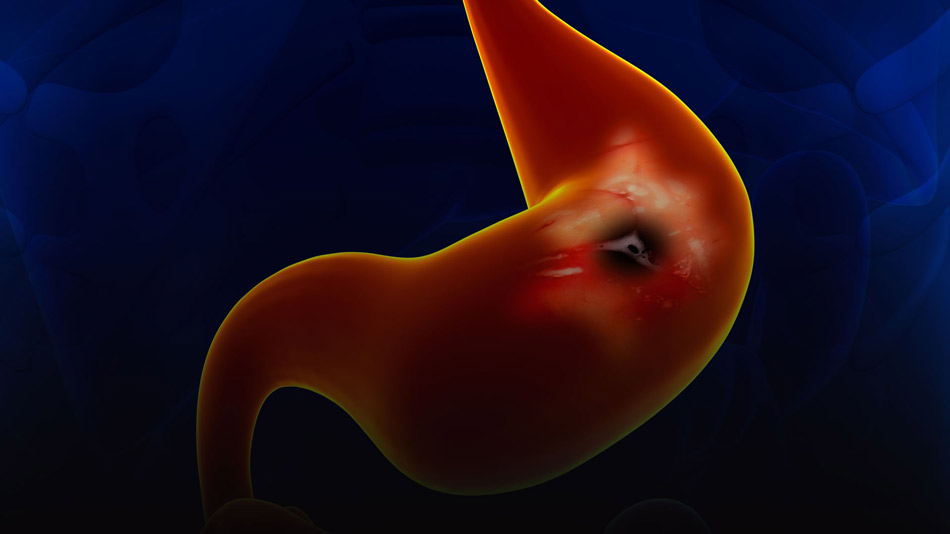

Cáncer gástrico. Revisión

Las terapias emergentes, como los nuevos tratamientos dirigidos y las inmunoterapias de última generación, son prometedoras para mejorar la supervivencia y la calidad de vida. Las futuras tendencias en el manejo del cáncer gástrico se centran en la medicina de precisión, los avances continuos en inmunoterapia, nuevos métodos de detección temprana y un enfoque multidisciplinario de la atención. Estas estrategias buscan mejorar la eficacia general del tratamiento y el pronóstico a nivel mundial.  Lancet, 1 de mayo de 2025